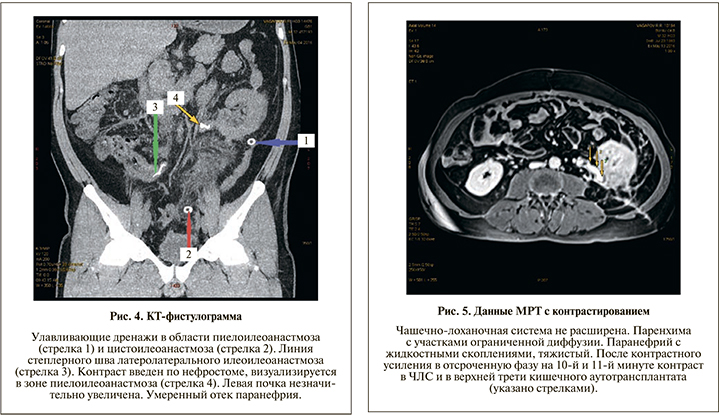

Ход операции. Под эндотрахеальным наркозом выполнена срединная лапаротомия. Рассечена брюшина по латеральному краю ободочной кишки, забрюшинная клетчатка по левому фланку деревянистой плотности с явлениями склероза. Мочеточник плохо дифференцировался, представлен рубцовым тяжом на всем протяжении. Левая почка несколько увеличена, мобилизована от паранефральной клетчатки, капсула рыхлая, под капсулой единичные апостемы (интраоперационная находка). Выполнена декапсуляция почки. Визуализирована лоханка, на уровне мочеточника – склероз. Лоханка рассечена на 1,2 см. Осуществлена мобилизация мочевого пузыря в ректовезикальном пространстве. Петля подвздошной кишки до 30 см мобилизована, отступя на 15 см от илеоцекального угла с сохранением сосудистой аркады, резецирована линейным степлером 30 мм. Непрерывность подвздошной кишки восстановлена формированием латеролатерального илеоилеоанастмоза в один ряд нитью ПДС 3/0. Изолированная петля подвздошной кишки перемещена в окне брыжейки сигмовидной кишки, расположена в изоперистальтическом направлении. Сформирован прямой пиелоилеоанастмоз непрерывным швом нитью Advantime 4/0. На заднюю губу анастомоза наложен дополнительный ряд швов. Дистальный конец подвздошного сегмента сформирован в виде конуса, наложен ручной однорядный илеоцистоанастмоз внебрюшинно, в подслизистом слое узловыми швами нитью Advantime 4/0 с дополнительной герметизацией мышечной частью стенки мочевого пузыря. Нефростомический дренаж установлен внебрюшинно и выведен в левой поясничной области. Поскольку полной герметизации нефростомы достичь не удалось (декапсуляция, рыхлая паренхима почки), через отдельные контрапертуры слева установлены улавливающие дренажи к пиелоилеоанастмозу и к цистоилеоанастмозу. Проведен контроль гемостаза, наложены послойные швы на рану. Асептическая наклейка. В послеоперационном периоде пациент получал антибиотикотерапию, прокинетическую, уросептическую терапию. Состояние постепенно улучшилось. Суточный диурез составил 1000–1200 мл. В течение 10 дней констатировали значительное отделяемое по улавливающим дренажам – от 160 до 300 мл в сутки, с постепенным снижением количества отделяемого. По нефростоме отделяемого ежесуточно до 60 мл мочи. Дренажи поэтапно удалены на 14-е сутки. Гипертермии не было. Контрольная КТ-фистулография выполнена 04.05.2016 (рис. 4): левая почка незначительно увеличена, вокруг почки отек паранефрия, чашечки умеренно расширены. 13.05.2016 выполнена МРТ с контрастом (рис. 5). В удовлетворительном состоянии в отсутствие жалоб, нормальной температуры тела и удовлетворительных лабораторных показателяей пациент выписан из отделения на 26-е сутки.

Осмотрен через 5 мес. после операции 05.10.2016. Состояние пациента удовлетворительное. Жалоб нет. Работает по специальности (мастер-нефтяник). При амбулаторно выполненном УЗИ от 04.10.2016: правая почка с конкрементом в средней чашечке до 0,7 см. Левая почка расположена несколько ниже нормы, контуры ровные, длина – 10 см, ширина – 6 см, толщина – 5 см. Толщина паренхимы – 1,8 см, эхогенность ее обычная, ЧЛС не расширена, в нижней чашечке конкремент до 0,7 см. Данные МРТ от 05.10.2016: ЧЛС не расширена, МР-признаки хронического пиелонефрита (рис. 6).